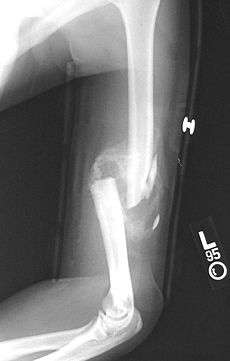

A displaced supracondylar fracture